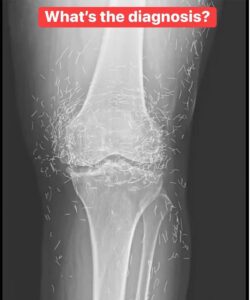

The 65-year-old woman from South Korea had previously been diagnosed with osteoarthritis, a condition in which the cartilage and bones within the joints degrade, causing pain and stiffness. However, when pain relievers and anti-inflammatory drugs didn’t alleviate the pain in her knees and only caused stomach discomfort, she had turned to acupuncture, the doctors wrote last week in the New England Journal of Medicine.

Acupuncture is an alternative medical practice that uses needles in order to purportedly stimulate certain points on the body, to alleviate pain or to treat a variety of diseases.